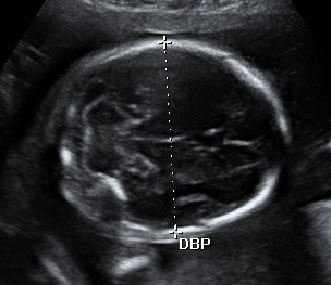

Mediante el ultrasonido, se mide el diámetro biparietal

Con una edad gestacional de 20 semanas, este bebé está muy entretenido con un dedo en la boca. En esta ecografía de la semana 20, la morfológica, el especialista también mide el diámetro parietal del feto para comprobar su correcto desarrollo.